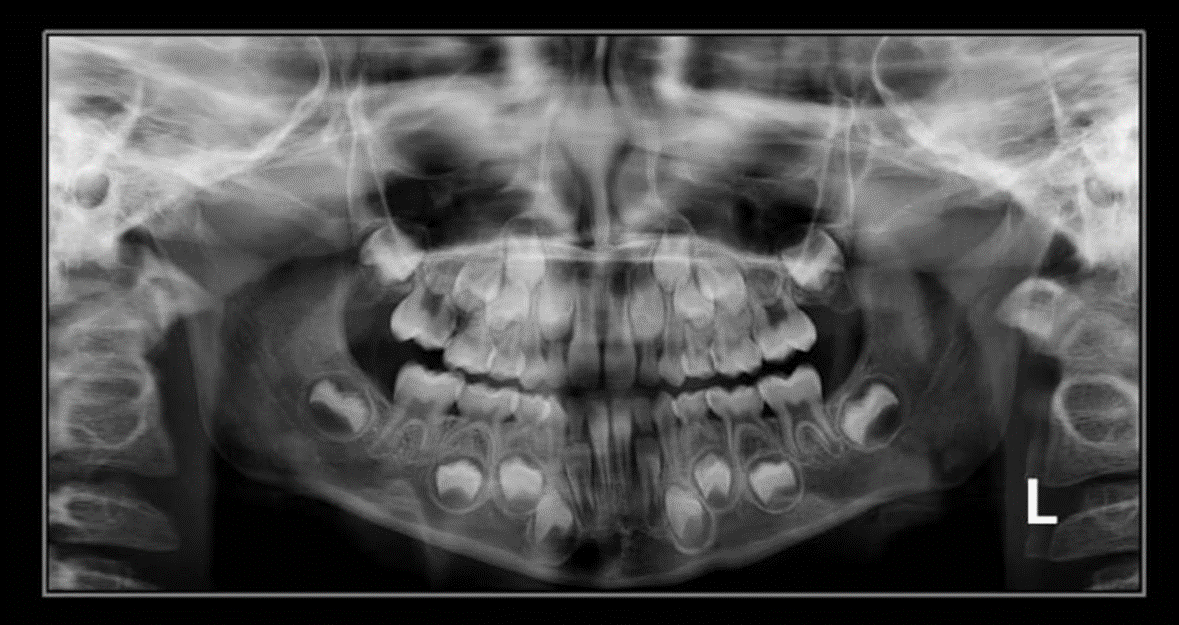

2. How old is the patient with the following X ray?